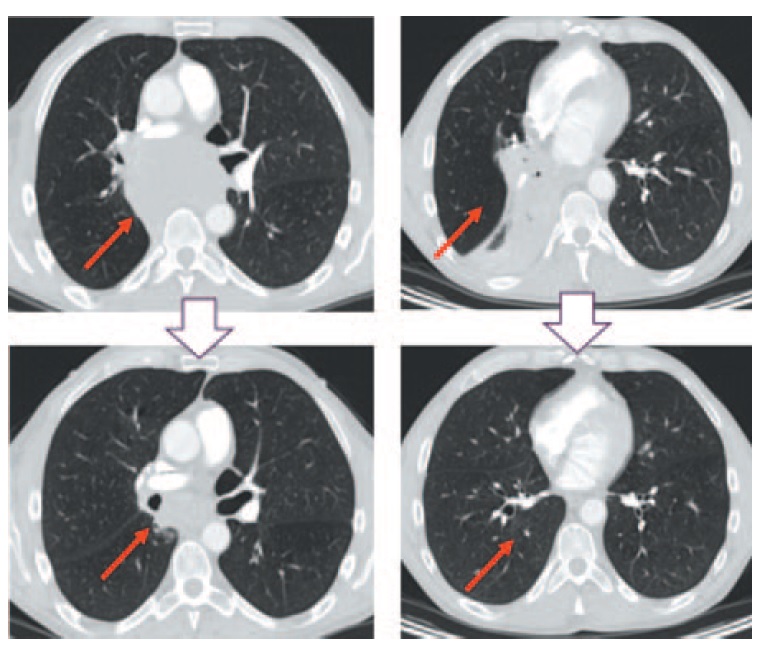

В августе 2017 г. выполнено первое контрольное обследование. По сравнению с МСКТ от июня 2017 г. при МСКТ от августа 2017 г. (рис. 3) отмечено уменьшение размеров опухолевого конгломерата в области корня правого легкого, переходящего на заднее средостение. Визуализировались отдельно расположенные фрагменты конгломерата – увеличенные бронхолегочные лимфоузлы размерами 24×20 и 20×12 мм, а также бифуркационные лимфоузлы размером 49×29 мм. Также отмечено восстановление просветов промежуточного, нижнезонального бронхов, В6. Правая легочная артерия прослеживалась отчетливо, признаки сужения отсутствовали, однако сохранялась небольшая компрессия нисходящей ветви правой легочной артерии. Также визуализировались отдельно расположенные внутригрудные лимфоузлы левой бронхолегочной и паратрахеальной групп без признаков увеличения. Отмечено уменьшение размеров параэзофагеального лимфоузла справа до 10×8 мм. В области брюшины сохранялись неорганные узловые образования, накапливающие контрастный препарат, размерами до 6 мм.

Рис. 3. МСКТ от августа 2017 г. Центральный рак правого легкого с метастазами во внутригрудных лимфоузлах. Отмечается частичный регресс заболевания по сравнению с МСКТ от июня 2017 г. / Fig. 3. MCT, August 2017. Centrally located right lung cancer with intrathoracic lymph nodes metastases. There is a partial regression of the disease by comparison with MCT of June 2017.

Таким образом, в соответствии с критериями RECIST 1.1, после 2 циклов ХТ+ИТ зафиксирован частичный регресс заболевания.

При контрольной МСКТ от ноября 2017 г. (рис. 4) сохранялись отдельно расположенные фрагменты опухолевого конгломерата, размеры их несколько уменьшились: бифуркационных лимфоузлов – до 38×17 мм, бронхолегочных лимфоузлов – до 18×11 мм и до 17×11 мм. Другие таргетные очаги, по сравнению с предшествующими исследованиями, не определялись.

Рис. 4. МСКТ от ноября 2017 г. в сравнении с МСКТ от июня 2017 г. / Fig. 4. MCT – November 2017 by comparison with MCT – June 2017.